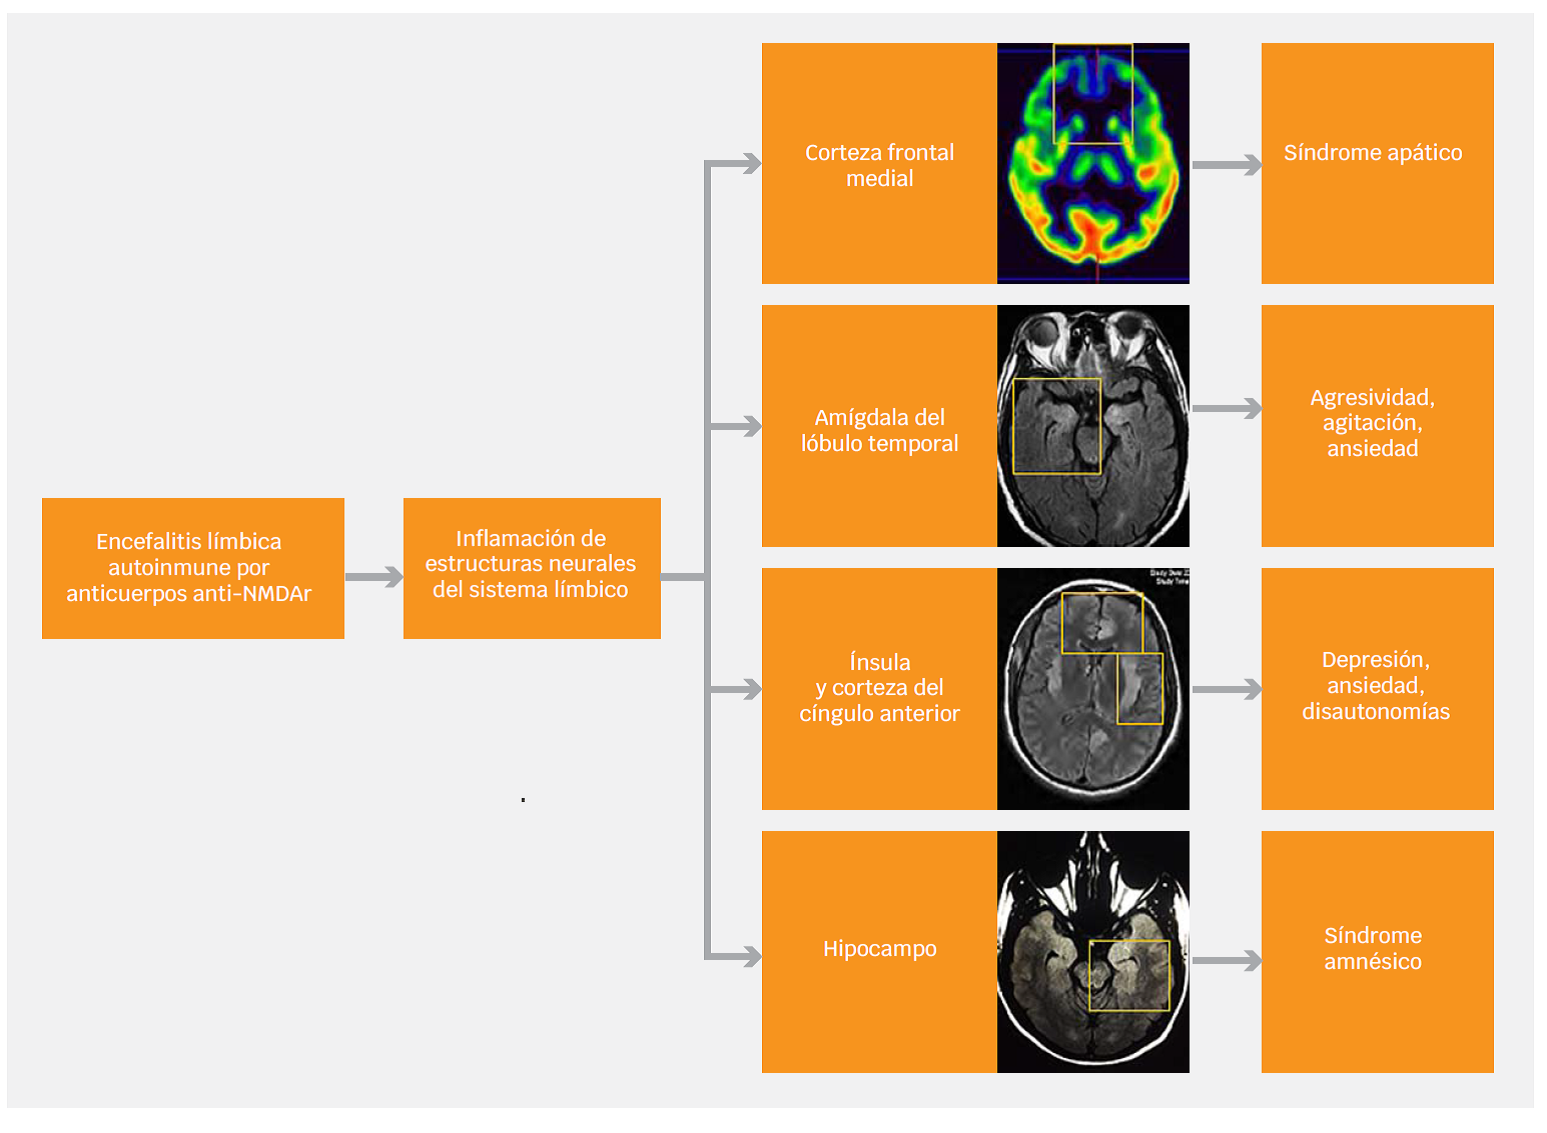

Alteraciones neuroanatómicas relevantes para entender la presentación neuropsiquiátrica

La encefalitis anti-NMDAr se asocia a anormalidades observables en los estudios de resonancia magnética. Un 50 % de los pacientes cursa con hiperintensidades en la secuencia FLAIR en regiones elocuentes para la regulación del comportamiento: lóbulo temporal medial (amígdala e hipocampo), ínsula, ganglios basales, corteza del cíngulo y corteza frontal.2,30 Estas estructuras se asocian a procesos cognitivos y emocionales, así como a la regulación del comportamiento en general, lo cual es clave para entender la formación de síntomas psiquiátricos prominentes en esta enfermedad31 (Figura 1). Algunos fenómenos, como la catatonia, son difíciles de explicar como resultado de anormalidades focales de la anatomía cerebral, por lo cual se proponen modelos de desequilibrio entre la vía directa y la vía indirecta en los circuitos frontoestriatales.32 En estos modelos, la internalización del receptor NMDA que resulta de la acción de los anticuerpos genera una desactivación de neuronas GABAérgicas en el estriado, lo cual, a su vez, provoca disregulación de la liberación de dopamina y de las proyecciones glutamatérgicas del tálamo.32 En el largo plazo, el daño hipocampal estructural se asocia a secuelas cognitivas, en particular mnésicas.33